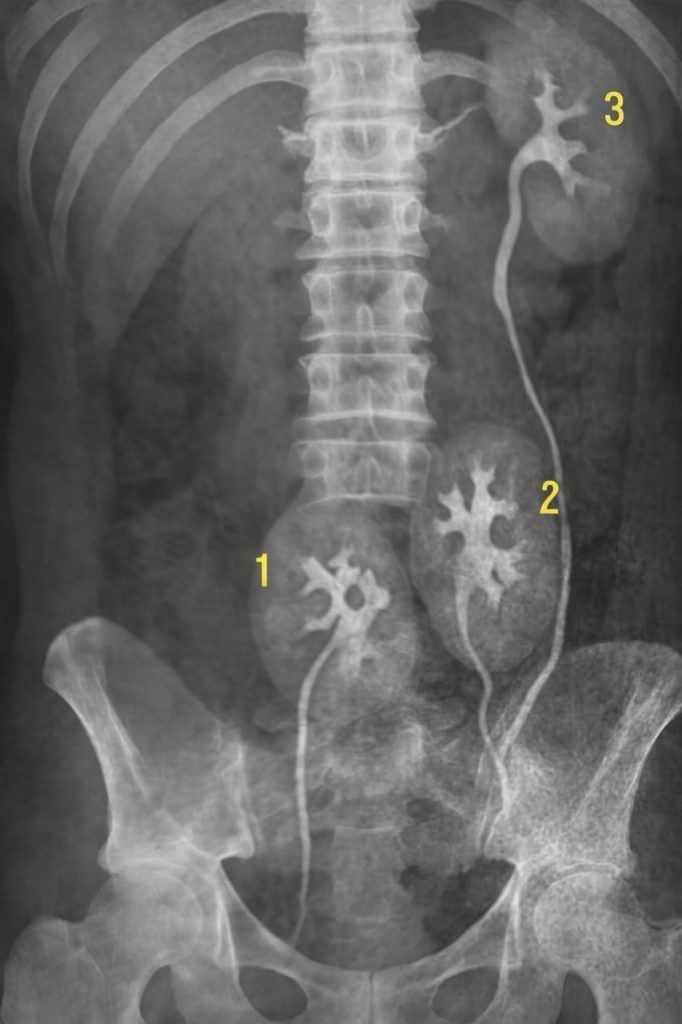

Tři ledviny.

Jedna navíc. Dokonale vytvořená. Funkční.